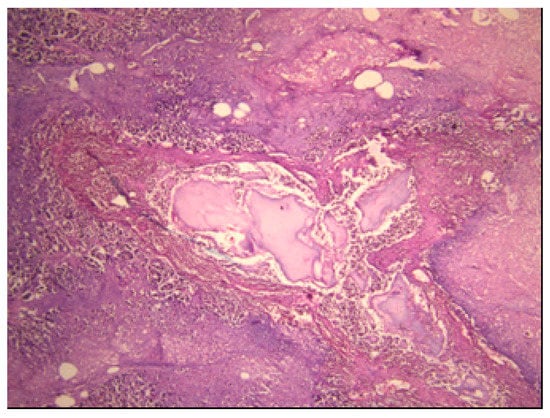

3.2. Histopathological Findings